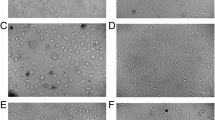

Damaged mitochondria are engulfed in the autophagosomes for their lysosomal degradation [17]; the effect of high glucose on autophagosome formation was investigated. Consistent with mitochondrial turnover, compared to normal glucose, high glucose decreased the number of the fluorescent autophagic vacuoles, as indicated by decreased autophagy dye staining (Fig. 2a and b), and MMP-9 inhibitor prevented decrease in the autophagosome formation (p > 0.05 vs NG). Termination of high glucose insult, in addition to preventing decrease in mitochondrial turnover, also failed to prevent decrease in autophagosomes. However, supplementing normal glucose, which had followed high glucose, with an MMP-9 inhibitor (HG-NG/Inh group), prevented decrease in the autophagosome formation, and the values in HG-NG/Inh group were significantly different from those in HG or HG-NG groups. L-glucose (20 mM) had no effect on the number of autophagosomes (Fig. 2a and b). Consistent with the immunofluorescence results, quantitative assay also showed a significant decrease in relative fluorescence intensity in high glucose, compared to normal glucose. Four days of normal glucose, after 4 days of high glucose (HG-NG group), had no beneficial effect on autophagosome formation; the values in HG and HG-NG groups were not different from each other. However, MMP-9 inhibitor addition during normal glucose incubation (HG-NG/Inh group) ameliorated decrease in autophagosome formation, and the values in NG, HG/Inh, and HG-NG/Inh were not different from each other (p > 0.05; Fig. 2c).

Autophagosome formation and reversal of high glucose insult. Autophagosomes were quantified in live cells using a cationic amphiphilic tracer to selectively label autophagic vacuole. a Cells mounted in DAPI-containing (blue) Vectashield mounting medium were imaged under a Zeiss Apotome at 20 × objective (scale bar = 20 µm). b Mean intensity of green fluorescence was plotted. Values are mean ± SD obtained from 3 to 4 cell preparations, with measurement made in 6 or more cells/preparation. c Plot of relative fluorescence intensity at 480 nm excitation and 530 nm emission wavelengths in arbitrary units (AU), considering values from normal glucose as 100%. NG and HG = 5 mM and 20 mM D-glucose; HG/Inh = 20 mM D-glucose or with MMP-9 inhibitor; HG-NG and HG-NG/Inh = 20 mM D glucose, followed by 5 mM D glucose, without or with MMP-9 inhibitor, respectively; L-G = 20 mM L-glucose; NG/Ripa = 5 mM D-glucose + Ripamycin. * and # p < 0.05 vs. NG or HG, respectively